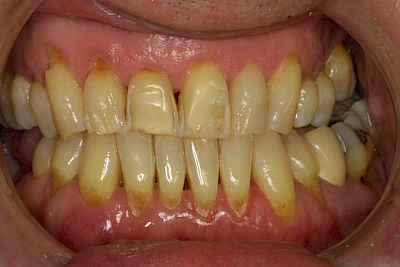

Über die Zeit können verschiedene Prozesse die Zahnhartsubstanzen aufzehren:

- Abnutzung durch Kauen (Abrasion) oder duch durch übermäßiges Knirschen bzw. Pressen (Attrition)

- Säurebedingte Auswaschung (Erosion)

- Knirschen bzw. Pressen und ungünstige Putztechnik (Druck): keilförmige Defekte

Die Zähne können dabei auf Reize (warm, kalt, süß, sauer) oder auch beim Zähneputzen empfindlich oder schmerzhaft sein. In allen diesen Fällen ist es sinnvoll, den Zahnarzt zu kontaktieren und das weitere Vorgehen abzustimmen.